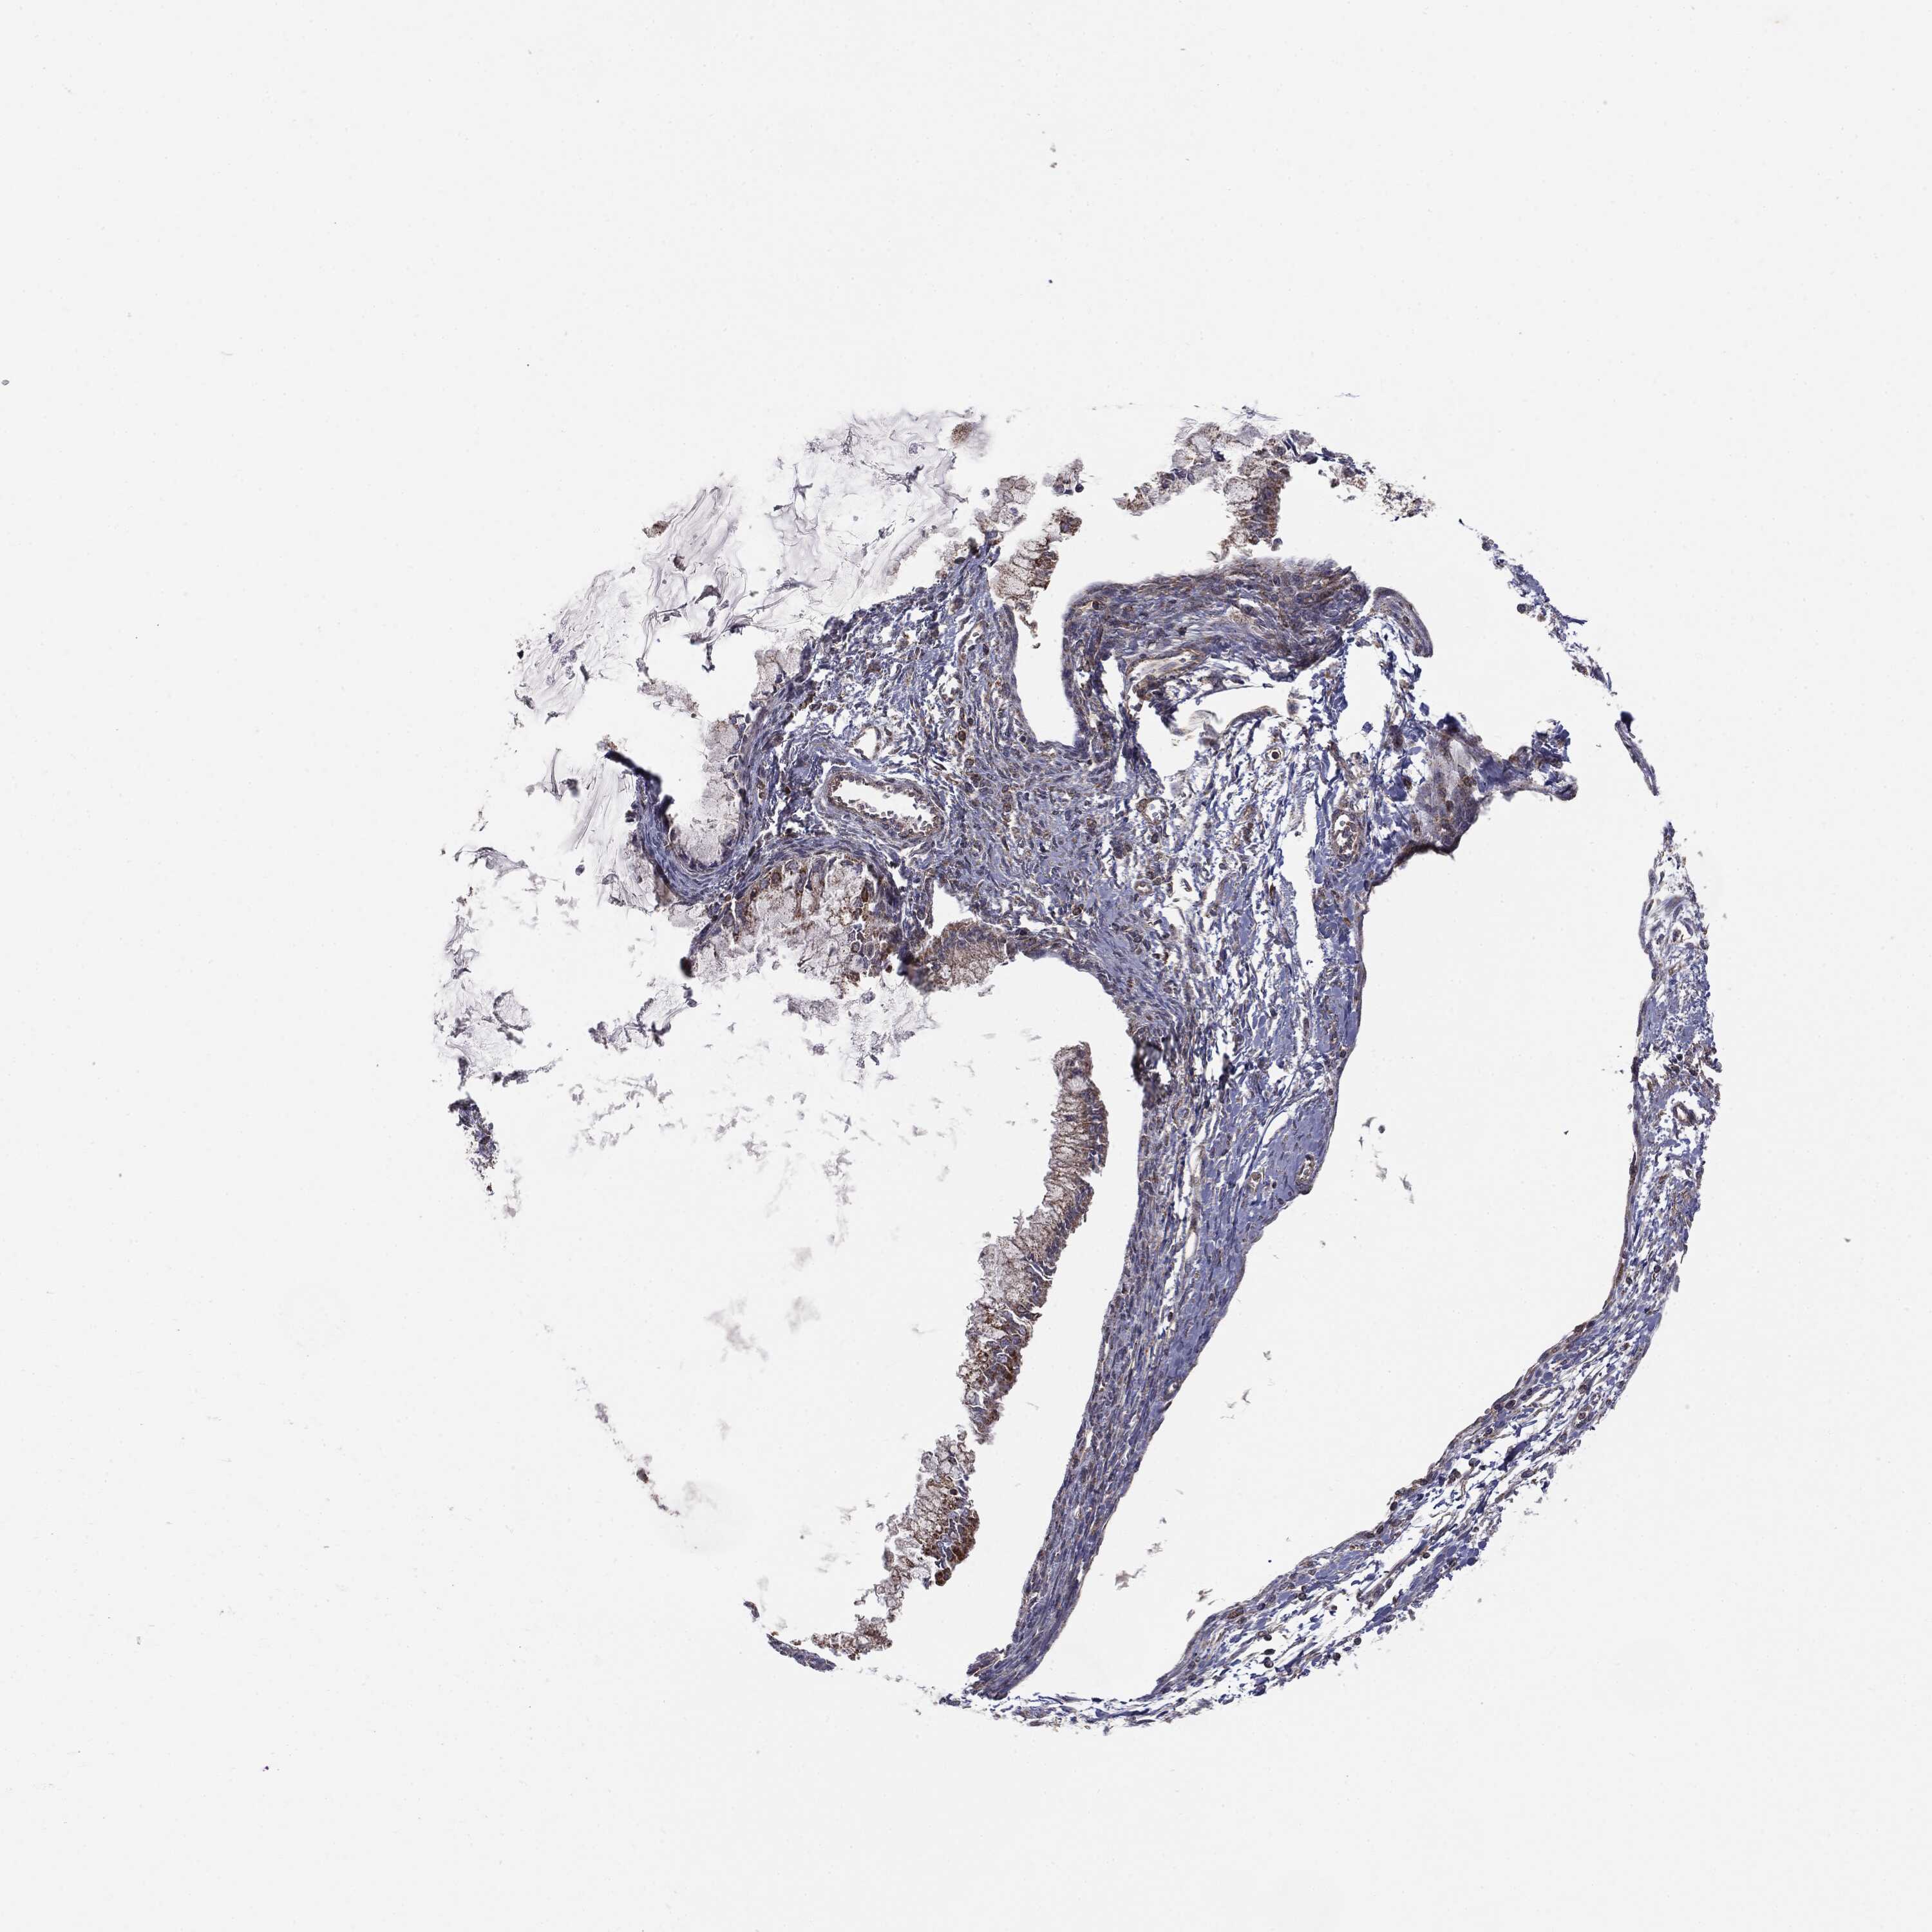

OVARIAN CANCER - Protein expressioni

A mouse-over function shows sample information and annotation data. Click on an image to view it in a full screen mode. Samples can be filtered based on level of antibody staining by selecting one or several of the following categories: high, medium, low and not detected. The assay and annotation is described here.

Note that samples used for immunohistochemistry by the Human Protein Atlas do not correspond to samples in the TCGA dataset.

Antibody stainingi

Antibody staining in the annotated cell types in the current human tissue is reported as not detected, low, medium, or high, based on conventional immunohistochemistry profiling in selected tissues. This score is based on the combination of the staining intensity and fraction of stained cells.

Each image is clickable and will lead to virtual microscopy that enables deeper exploration of all samples and also displays staining intensity scores, fraction scores and subcellular localization as well as patient and tissue information for each sample.

CAB069425

Cystadenocarcinoma, serous, NOS